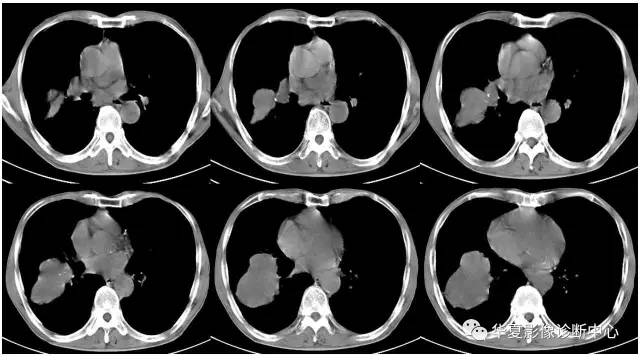

右肺原始神经外胚层肿瘤PNET一例CT